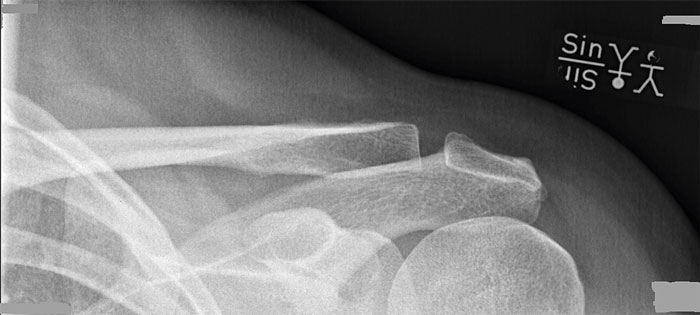

Klavikelfraktur. Bilden visar åt vilket håll frakturen dislokeras.

Akromioklavikularleden och laterala klavikeln visualiseras bäst med Zancas projektion, som tas genom att rikta röntgenstrålen 15 grader kraniellt. Diafysära frakturer visualiseras ofta bäst i en anteroposterior projektion, och frakturer i övergången mellan mellersta och laterala tredjedelen i en 45 graders sned (uppåtriktad) projektion.